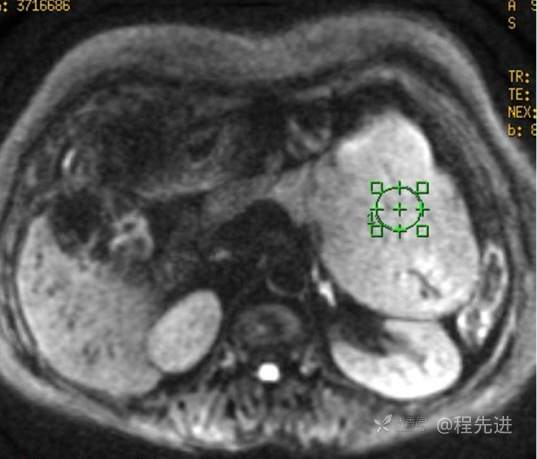

MR

T1压脂